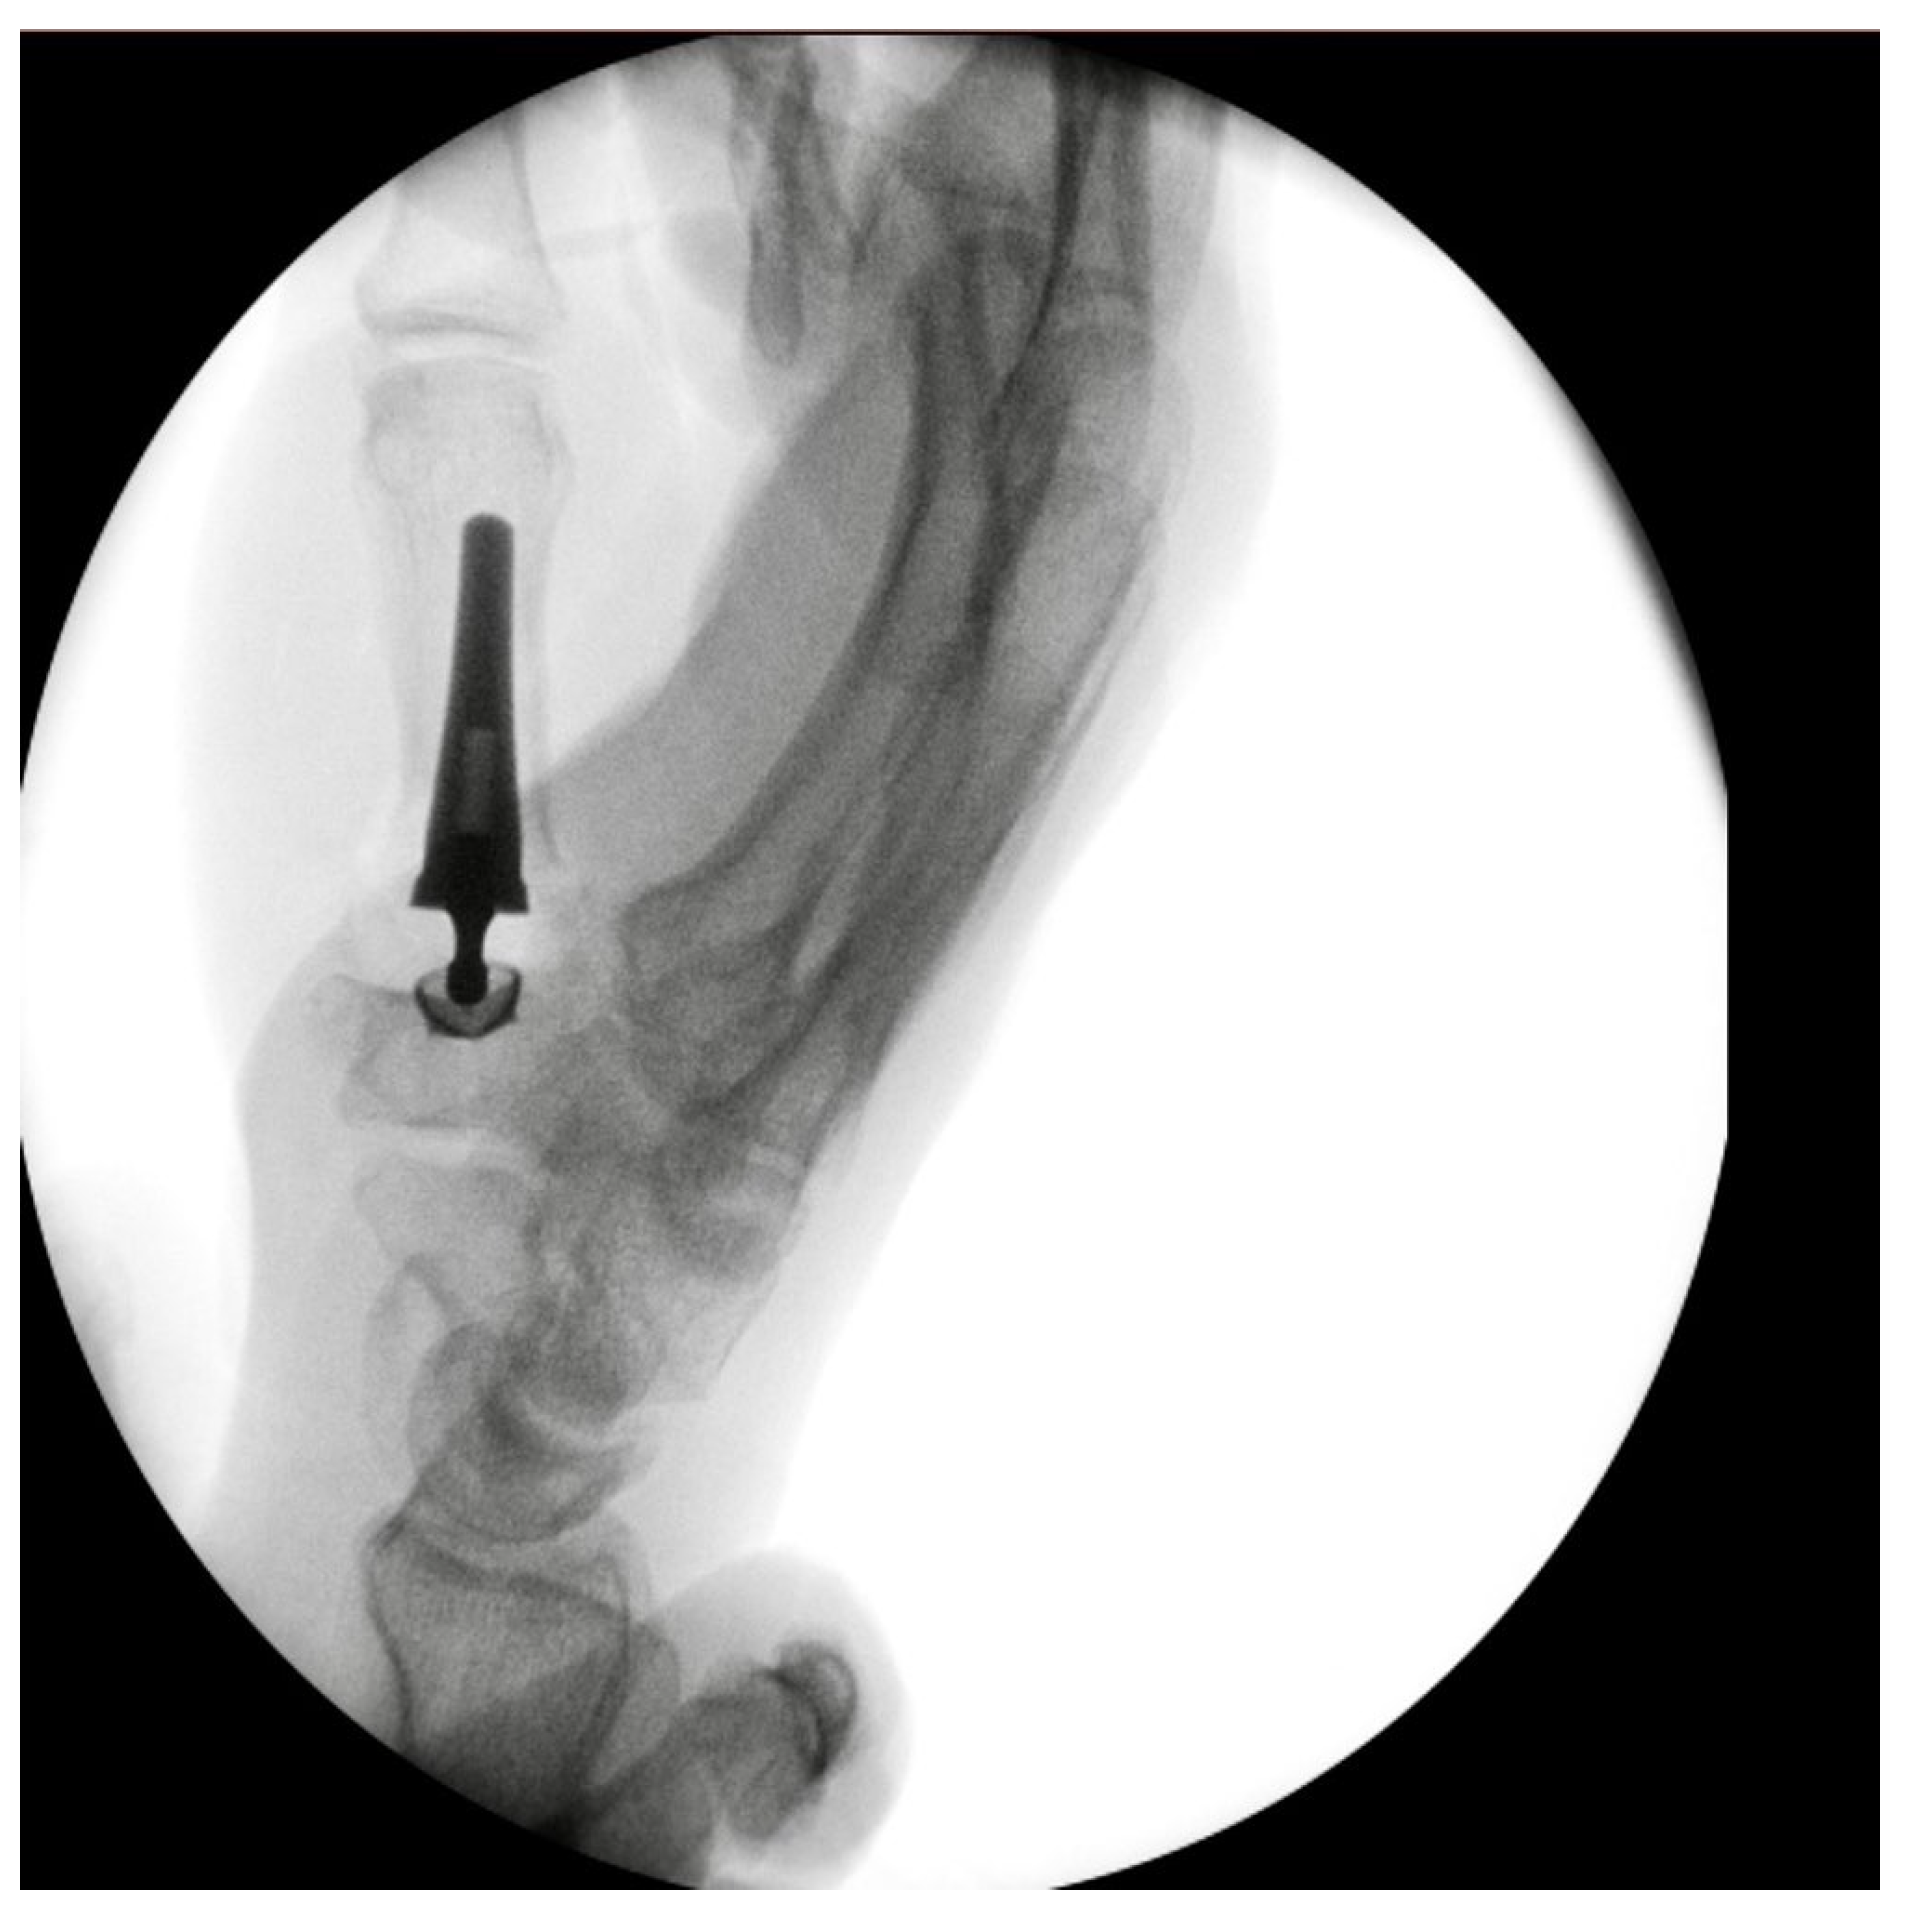

Primary Trapeziometacarpal (TMC) Arthroplasty for Bennett Fracture in Setting of Severe Thumb Osteoarthritis: A Case Report

2. Case Report